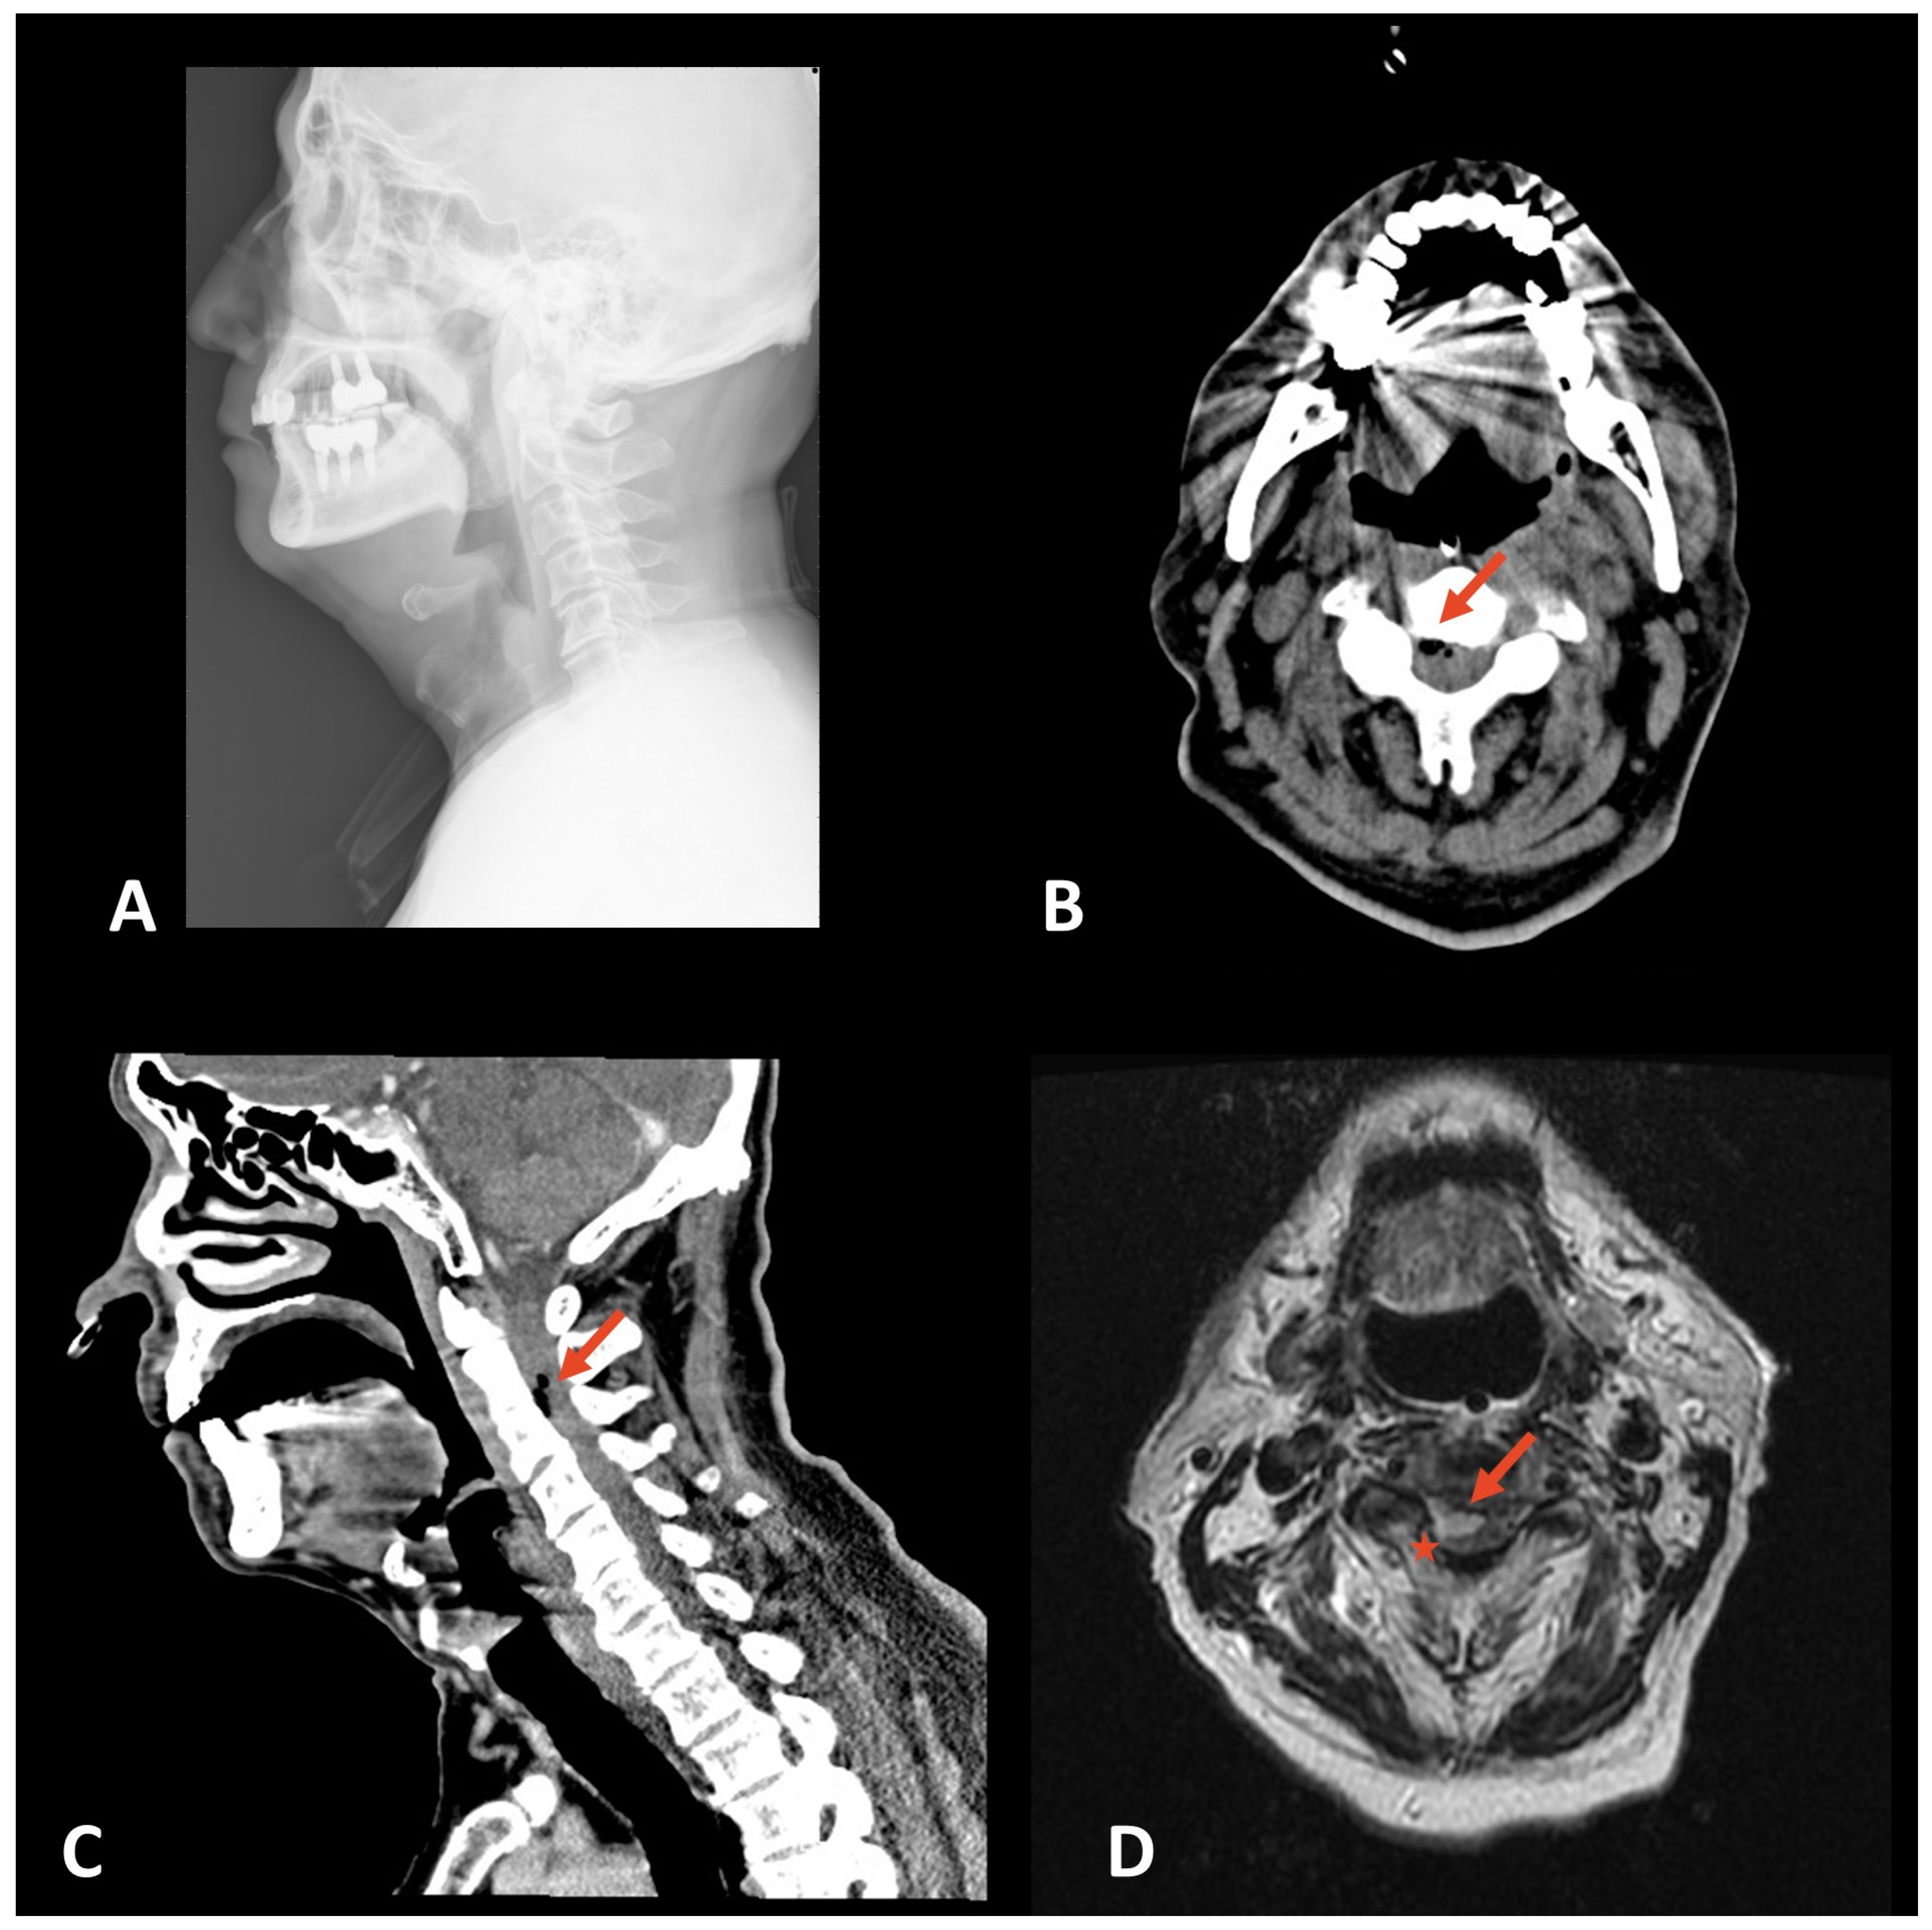

Figure 1. Radiological findings in a patient with spinal infection. (A) Lateral cervical spine X-ray manifesting normal bony structure without visible gas formation in the soft tissue area. (B) Axial CT scan showing epidural soft tissue thickening with air bubbles at cervical spine levels C2 to C3 (Arrow). (C) Sagittal CT highlighting the same abnormalities (Arrow). (D) Axial T2-weighted MRI illustrating high signal changes in the spinal cord from cervical levels C1 to C3 indicative of swelling and edema (red star), and low signal intensities in the epidural space suggestive of gas formation (red arrow).

A 63-year-old male, previously treated for left tonsil and hypopharyngeal cancer, presented to the emergency department with persistent neck pain lasting three days. A neurological examination revealed decreased muscle power in the right upper limb, affecting the patient’s ability to move against gravity. Laboratory findings showed elevated inflammatory markers, including C-reactive protein (19 mg/dL), procalcitonin (7.4 ng/mL), and erythrocyte sedimentation rate (131 mm/hr; normal: 0–20 mm/hr). A differential leukocyte analysis revealed neutrophilia (81%; normal: 55–75%), monocytosis (12%; normal: 0–10%), and lymphocytopenia (6%; normal: 20–40%). The Monocyte Distribution Width (MDW) was also increased at 31.13 (normal: <20). A cervical spine X-ray was performed during the initial investigation and manifested no evidence of gas formation (Figure 1A). Computed tomography (CT) of the brain and cervical spine demonstrated epidural soft tissue thickening and air bubbles at cervical levels C2 to C3, indicative of possible infectious or postoperative changes (Figure 1A,B). Subsequent urgent magnetic resonance imaging (MRI) confirmed high signal changes on T2-weighted images from C1 to C3, signaling swelling and edema in the spinal cord. Low signal intensities in the epidural space, indicated of gas formation, were also noted (Figure 1C). A neurosurgical consultation was promptly obtained, and a laminectomy was performed, revealing and decompressing a bulging spinal cord. During surgery, a pus culture from the epidural abscess was performed, but no microbiota was isolated after a 5-day incubation. The patient continued on antibiotic therapy after blood cultures yielded positive for Streptococcus constellatus.